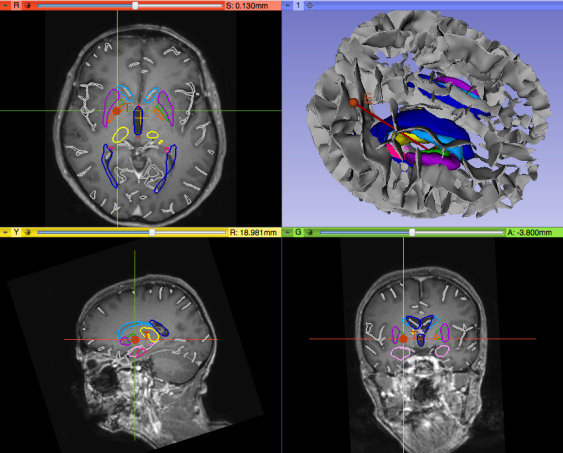

Pydbs.png

215 KB